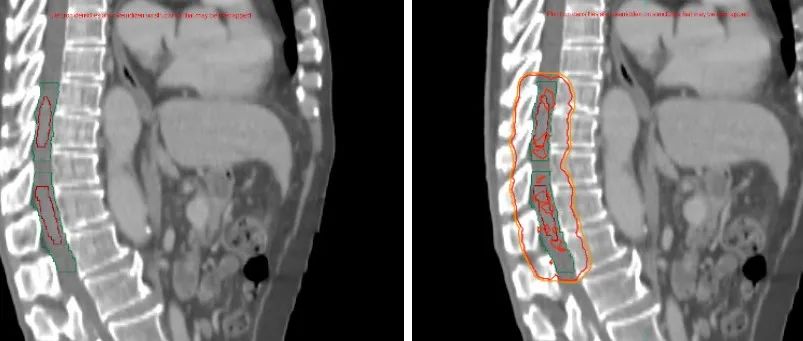

【病例分享】脊髓内转移瘤放疗一例(神经放疗系列四)---浙二神外周刊(第369期)